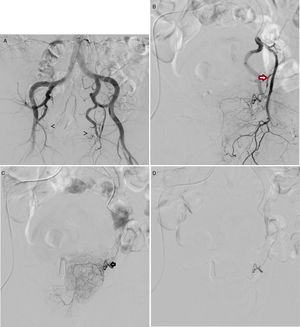

The access route used was either common femoral (Fig. 1) or radial with local anaesthesia.

(A) Pelvic arteriogram prior to the selective embolisation of prostate arteries, in which the origin of both arteries is indicated with arrows. B) Selective arteriogram of left internal iliac artery, with 10° cranial and 35° ipsilateral angulation, with the aim of identifying the exit of the inferior vesical artery/prostate artery (arrow). C) Selective catheterisation, with microcatheter in the left prostatic artery (arrow). Prior to the embolisation with 250-micron microparticles. D) Follow-up angiogram post-embolisation, which shows the vessel to be completely sealed; in this case the left prostatic artery.